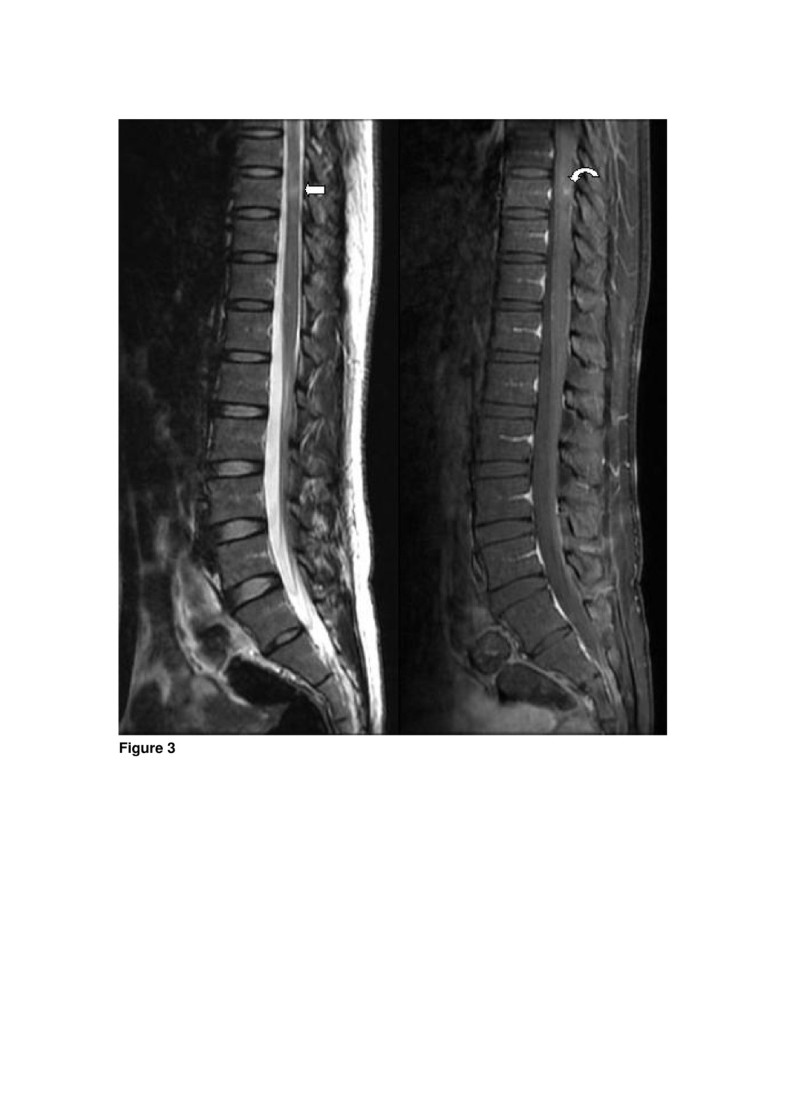

Multiple sclerosis presenting initially with a worsening of migraine Shooting Head Pain Multiple Sclerosis An ice pick headache may cause. while headaches are not a direct, primary symptom of multiple sclerosis, at least half of people with the disease experience head. An ms lesion is an area in the nervous. Pain can occur as an acute syndrome, but. science suggests that, in some people, autoimmune disease and ice pick headaches. It happens. Shooting Head Pain Multiple Sclerosis.